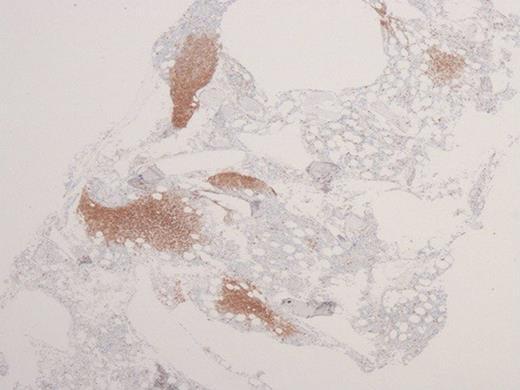

Immune checkpoint inhibitors (ICIs), including anti-cytotoxic T-lymphocyte antigen 4 (anti-CTLA-4) and anti-programmed death receptor-1/ligand-1 (anti-PD-1/anti-PD-L1) caused a breakthrough in oncology and significantly improved therapeutic outcomes in cancer patients. ICIs generate a specific reaction in T cells, directed against antigens on cancer cells, leading to their damage and death. Through similar or the same antigens, activated lymphocytes may also have a cytotoxic effect on healthy cells, causing development of specific adverse effects - so-called immune-related adverse events (irAEs). We present the case report of a 56 year old patient with disseminated melanoma. During treatment with immunotherapy (anti PD-1), neutropenic fever and pancytopenia occurred. Trepanobiopsy of the bone marrow was performed to determine the cause of pancytopenia. Histopathological assessment of bone marrow combined with immunophenotype investigations may explain the cause of hematological disorders occurring in the course of treatment with ICIs, and support the choice of an appropriate treatment, directly translated into positive outcomes.

免疫检查点抑制剂(ICIs),包括抗细胞毒性T淋巴细胞抗原4(抗CTLA-4)和抗程序性死亡受体-1/配体-1(抗PD-1/抗PD-L1),在肿瘤学领域带来了突破,并显著改善了癌症患者的治疗效果。ICIs在T细胞中引发针对癌细胞上抗原的特异性反应,导致癌细胞受损和死亡。通过相似或相同的抗原,活化的淋巴细胞也可能对健康细胞产生细胞毒性作用,从而引发特定的不良反应——即所谓的免疫相关不良事件(irAEs)。我们报告了一例56岁播散性黑色素瘤患者的病例。在接受免疫治疗(抗PD-1)期间,出现了中性粒细胞减少性发热和全血细胞减少。进行了骨髓环钻活检以确定全血细胞减少的原因。骨髓组织病理学评估结合免疫表型研究,可能解释ICIs治疗过程中发生血液系统疾病的原因,并支持选择合适的治疗方法,直接转化为积极的治疗结果。